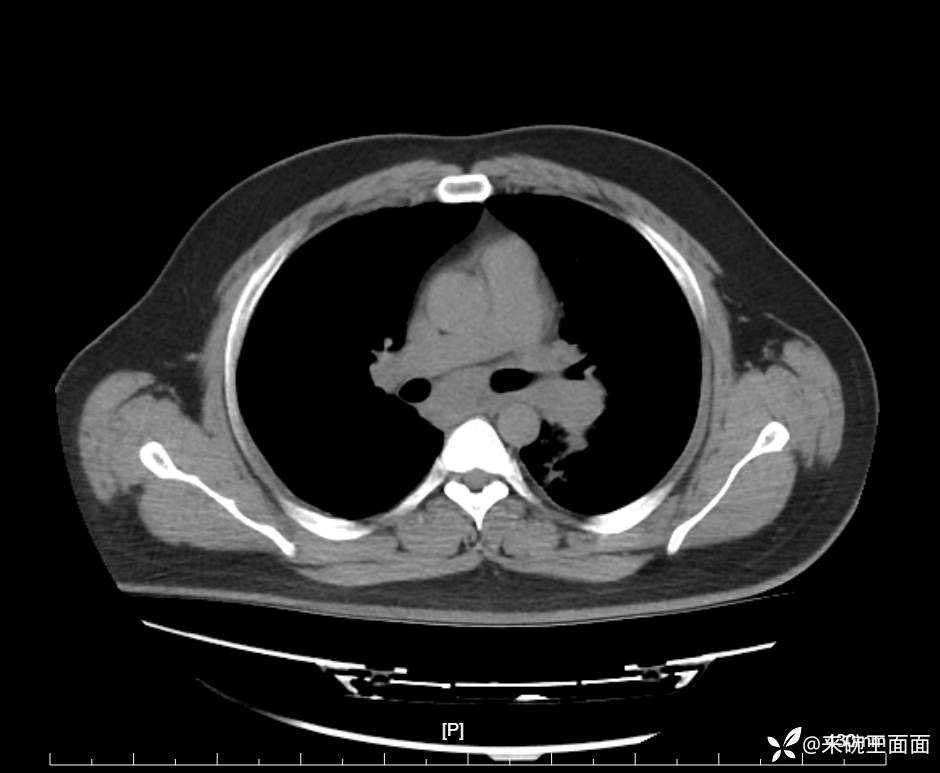

性别:男

年龄:27岁

主诉:胸闷胸痛数月余,休息后可自行缓解,无咯血症状。

个人史:数年吸烟史,具体不详。